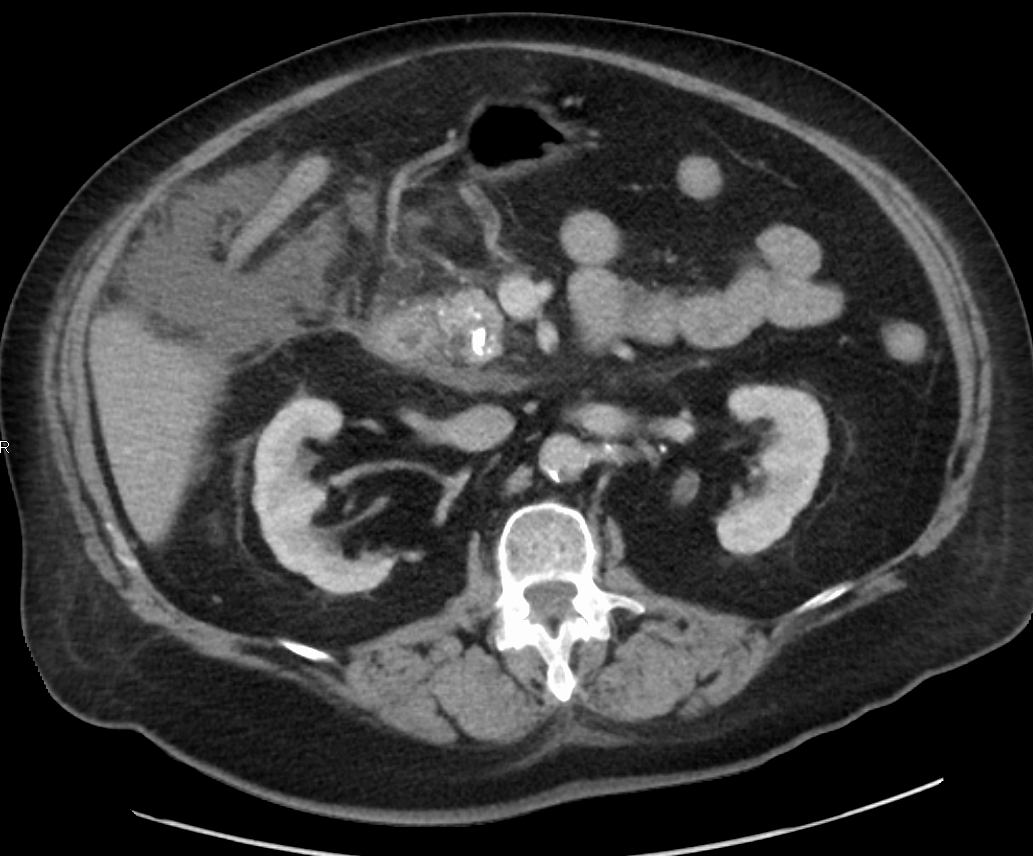

조영제를 사용한 CT 스캔은 일반적으로 통증이 시작된 지 48시간 이상 지난 후에 시행한다. 이는 췌장 조직의 괴사 여부와 췌장 주변의 액체 저류 상태를 평가하고 질병의 중증도를 예측하는 데 도움이 된다. CT 스캔을 너무 일찍 시행하면 실제보다 상태가 괜찮다고 잘못 판단할 위험이 있다.[33]

- '''복부 CT''': 일반적으로 췌장염 증상 발생 후 48시간 이상 지난 시점에서 조영제를 사용하여 CT 촬영을 시행한다. CT는 췌장 조직의 괴사 여부, 췌장 주변의 액체 고임 등을 평가하고 질병의 중증도를 판단하는 데 중요한 정보를 제공한다. 너무 이른 시기에 CT 검사를 시행하면 병의 상태를 정확히 반영하지 못하여 잘못된 판단을 내릴 수 있다.[33]